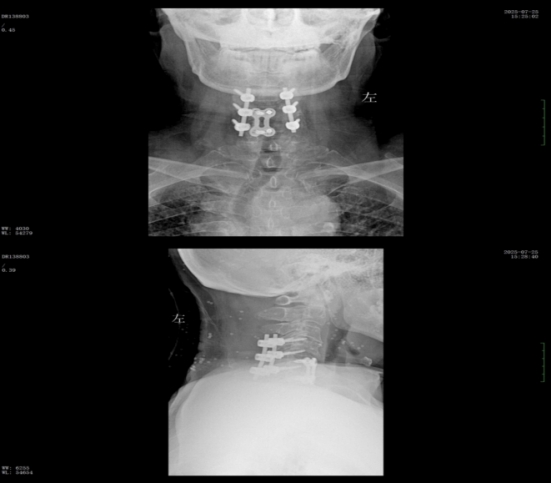

經(jīng)過精準(zhǔn)手術(shù)和術(shù)后系統(tǒng)的康復(fù)治療,患者神經(jīng)功能得到明顯恢復(fù),四肢肌力及感覺逐步改善,術(shù)后肌力達到IV級左右。復(fù)查X線顯示內(nèi)固定位置理想,患者非常滿意。出院之際,患者及家屬對衡陽市中心醫(yī)院的醫(yī)療技術(shù)、護理服務(wù)及醫(yī)聯(lián)體轉(zhuǎn)診效率均給予高度評價。

wps2.jpg

術(shù)后x線內(nèi)固定位置理想